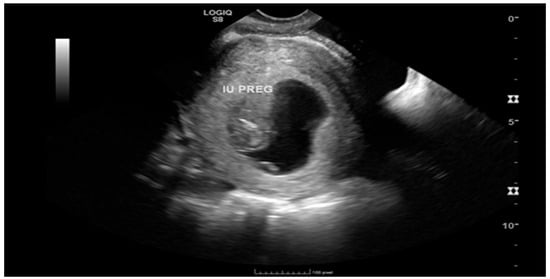

Ruptured Heterotopic Pregnancy: Laparoscopic Management, Preserving Intrauterine Viability

Pregnancy (HP), defined as the coexistence of intrauterine and ectopic gestations, is a rare condition, especially in spontaneous conception, but it is a life-threatening obstetric emergency when rupture occurs, with a reported maternal mortality rate of 0.03%. Diagnosis is often delayed because confirmation of an intrauterine pregnancy can mask clinical signs of a concurrent ectopic gestation. Early recognition and prompt surgical intervention are therefore critical to maternal safety and preservation of intrauterine viability. This case highlights the diagnostic challenges and successful management of a spontaneous ruptured heterotopic pregnancy. Case presentation: A 34-year-old Middle Eastern woman, gravida 4, with a spontaneous conception, presented with sudden severe lower abdominal pain and signs of acute hemoperitoneum (hypotension, tachycardia, and marked peritoneal signs). Transvaginal ultrasound demonstrated a viable intrauterine pregnancy at 9 weeks 4 days gestation, together with a ruptured left tubal ectopic pregnancy of similar gestational age. The patient underwent urgent laparoscopic left salpingectomy with evacuation of approximately 1200 mL of intraperitoneal blood and clots. Postoperatively, she developed significant anemia (hemoglobin drop from 11.2 g/dL on admission to 6.5 g/dL) requiring transfusion of four units of packed red blood cells. Serial ultrasonographic follow-up confirmed ongoing viability of the intrauterine pregnancy, which ultimately resulted in a live birth at term. Progressive resolution of the postoperative pelvic hematoma was also noted. Conclusions: Ruptured heterotopic pregnancy remains a diagnostic and therapeutic challenge. This case, along with a synthesis of the contemporary literature, demonstrates that a high clinical index of suspicion, timely ultrasound diagnosis, and immediate minimally invasive surgical management are paramount. Furthermore, rigorous postoperative monitoring and resuscitation, including targeted transfusion, are essential to achieve maternal stabilization while allowing continuation of a viable intrauterine pregnancy, with reported live birth rates exceeding 70% following timely intervention. Full article